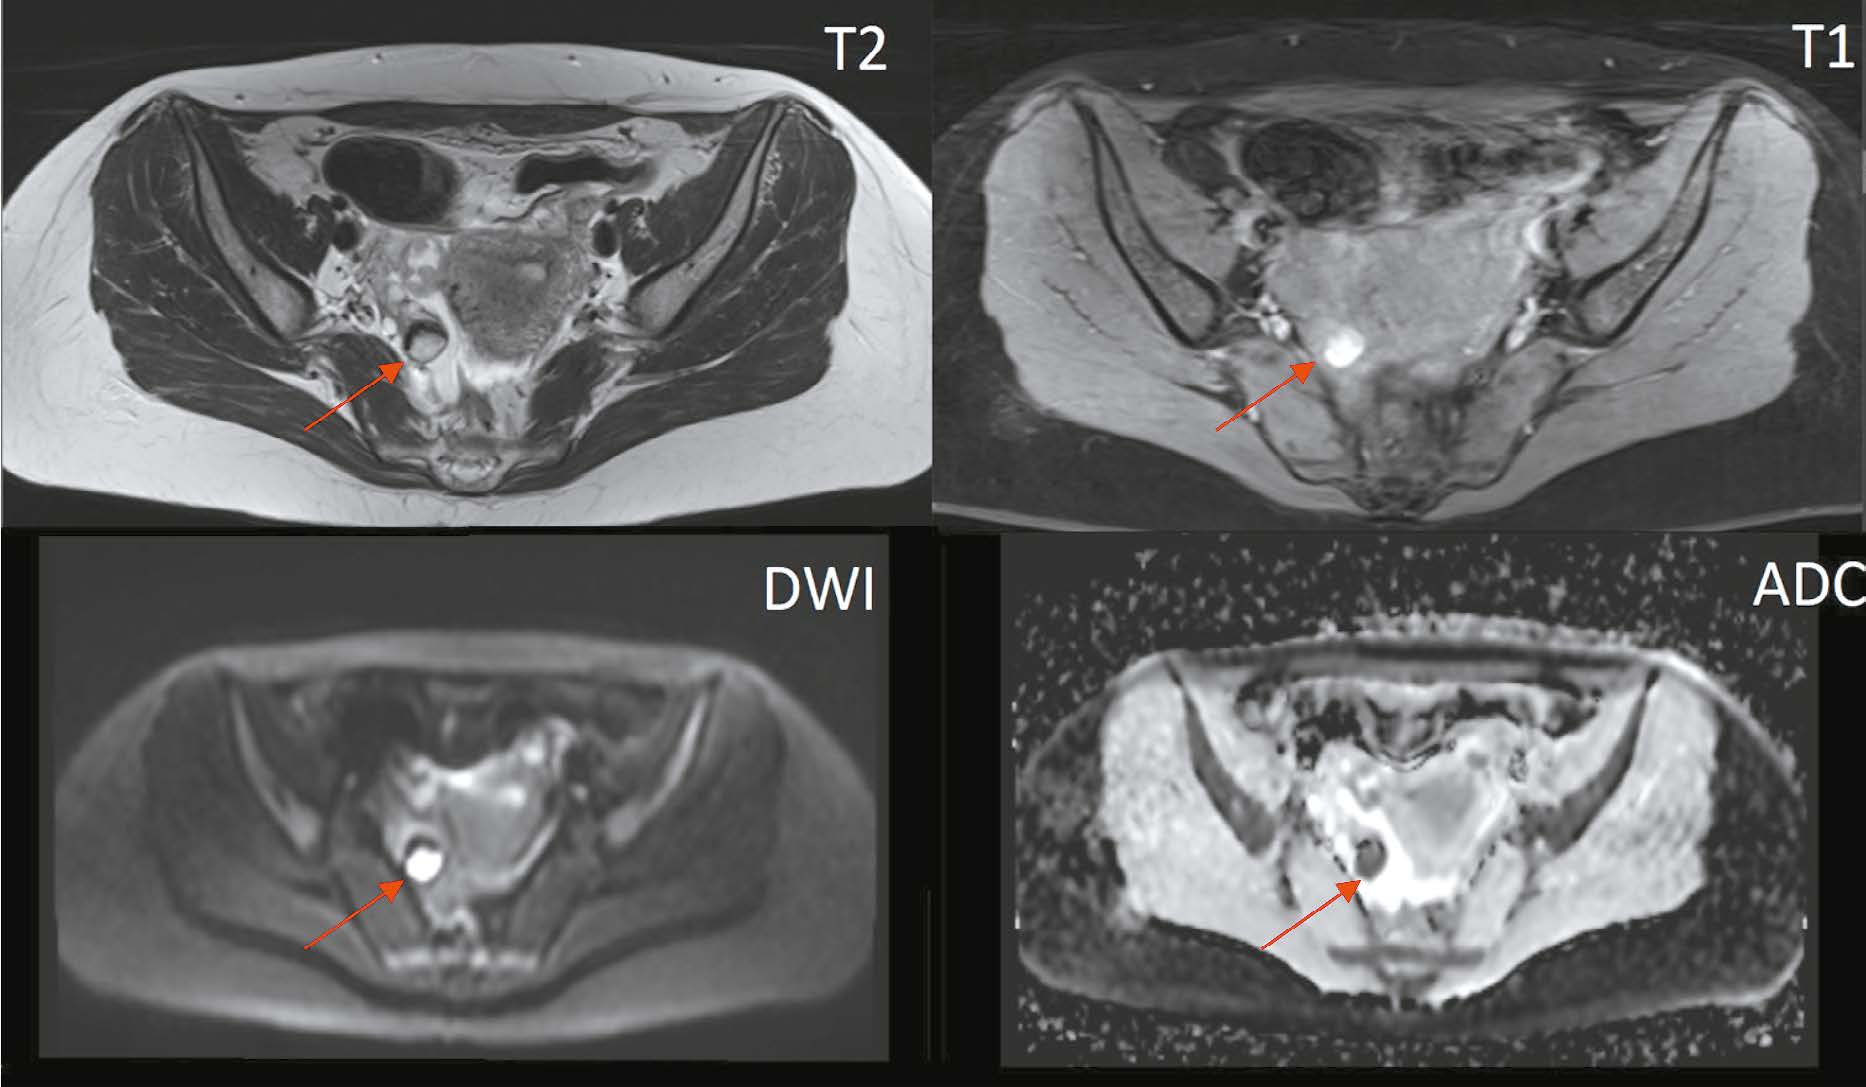

Serous adenocarcinoma of fallopian tubes is an extremely rare and difficult to diagnose type of cancer of the female reproductive system. This condition is often asymptomatic or has a non specific clinical presentation including serosanguineous vaginal discharge and colic like pain in the lower abdomen and pelvis. These symptoms are reported in the literature as the Latzko’s triad and are considered pathognomonic for tubal cancer, but their combination is observed in less than 15% of patients. The low incidence and lack of the pathognomonic clinical presentation lead to many diagnostic errors or detection of advanced disease, which significantly worsens the patient’s prognosis. An accurate surgical diagnosis is made in only 4% of cases. This case report describes serous adenocarcinoma of fallopian tubes with all signs of the Latzko’s triad and MRI suggestive of serous adenocarcinoma of fallopian tubes at a preoperative stage.